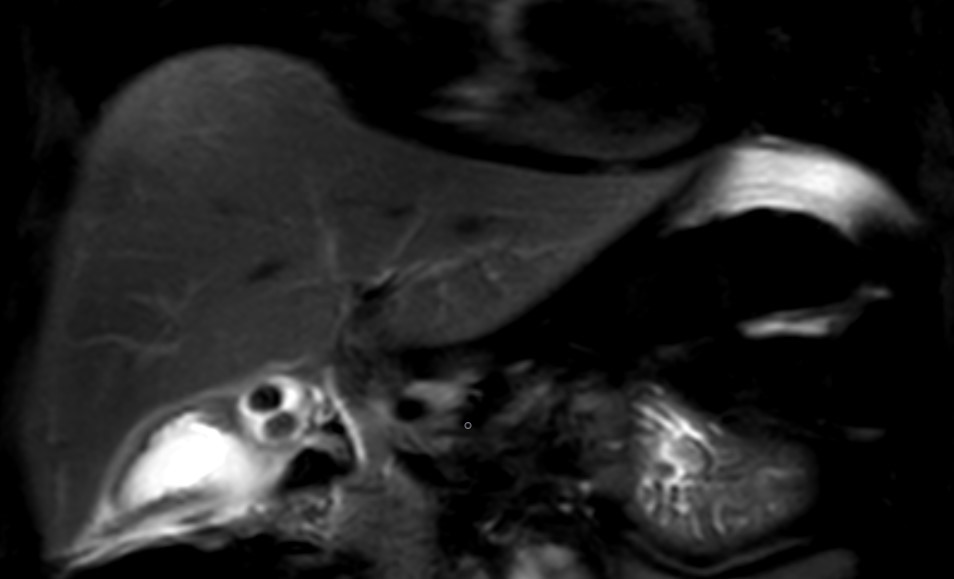

Figure 1. Two gallbladers and the stones in them, which can be seen in the T2 magnetic resonance image

Abdominal ultrasound (US) showed a thickened wall of gallbladder and the lithiasic cholecystitis in GB which rolled around itself. She was further investigated with Magnetic resonance cholangio pancreatography (MRCP), which confirmed the cholecystitis on GB which rolled around itself and revealed normal CBD (Figure 1). A decision was made to procedure with a laparoscopic cholecystectomy. Intaoperatively two gallbladders enveloped in a single peritoneal membrane and two cystic duct was observed (Figure 2). It was an operative suprize because her MRCP did not reveal any evidence of duplication of the gallbladder. Intaroperative cholangiography was decided to identify the biliary tree. This cholangiogram confirmed the presence of two cystic ducts opening in the CBD (Figure 3). After ligature of two separate cystic duct a challenging laparoscopic cholecystectomy was performed successfully.